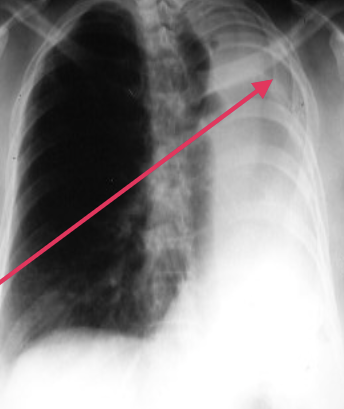

• The left hemithorax is opaque.

• There is a shift of the heart and trachea toward that side indicating volume loss

• The left 5th rib has been resected - to perform the operation